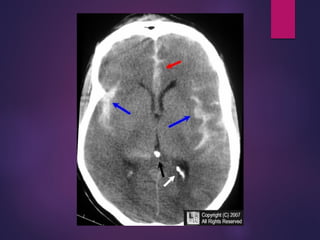

CT Scan

 Intraventricular Hemorrhage (IVH)

 Hydrocephalus

 Intracerebral hematoma (ICH)

 Brain edema

 Infarction caused by vasospasm